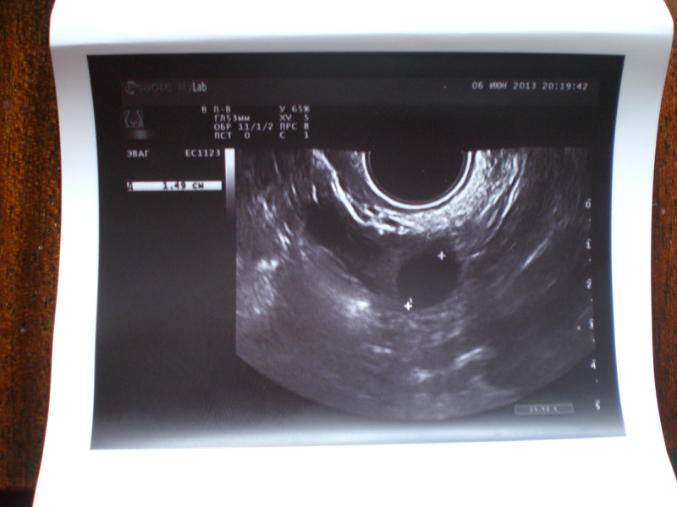

6.06 делала узи малого таза.. узистка говорит что всё плохо, в обоих яичниках кисты!!!!!!!! почему тогда тесты на овуляцию полосяться?

посмотрела фотку-у вас прям динамика хорошая-старайтесь активнее)

Узи от 6 июня? Кисты ставила фолликулярные? Могли лопнуть, совулировать. Сходите через денек на узи посмотрите, что там